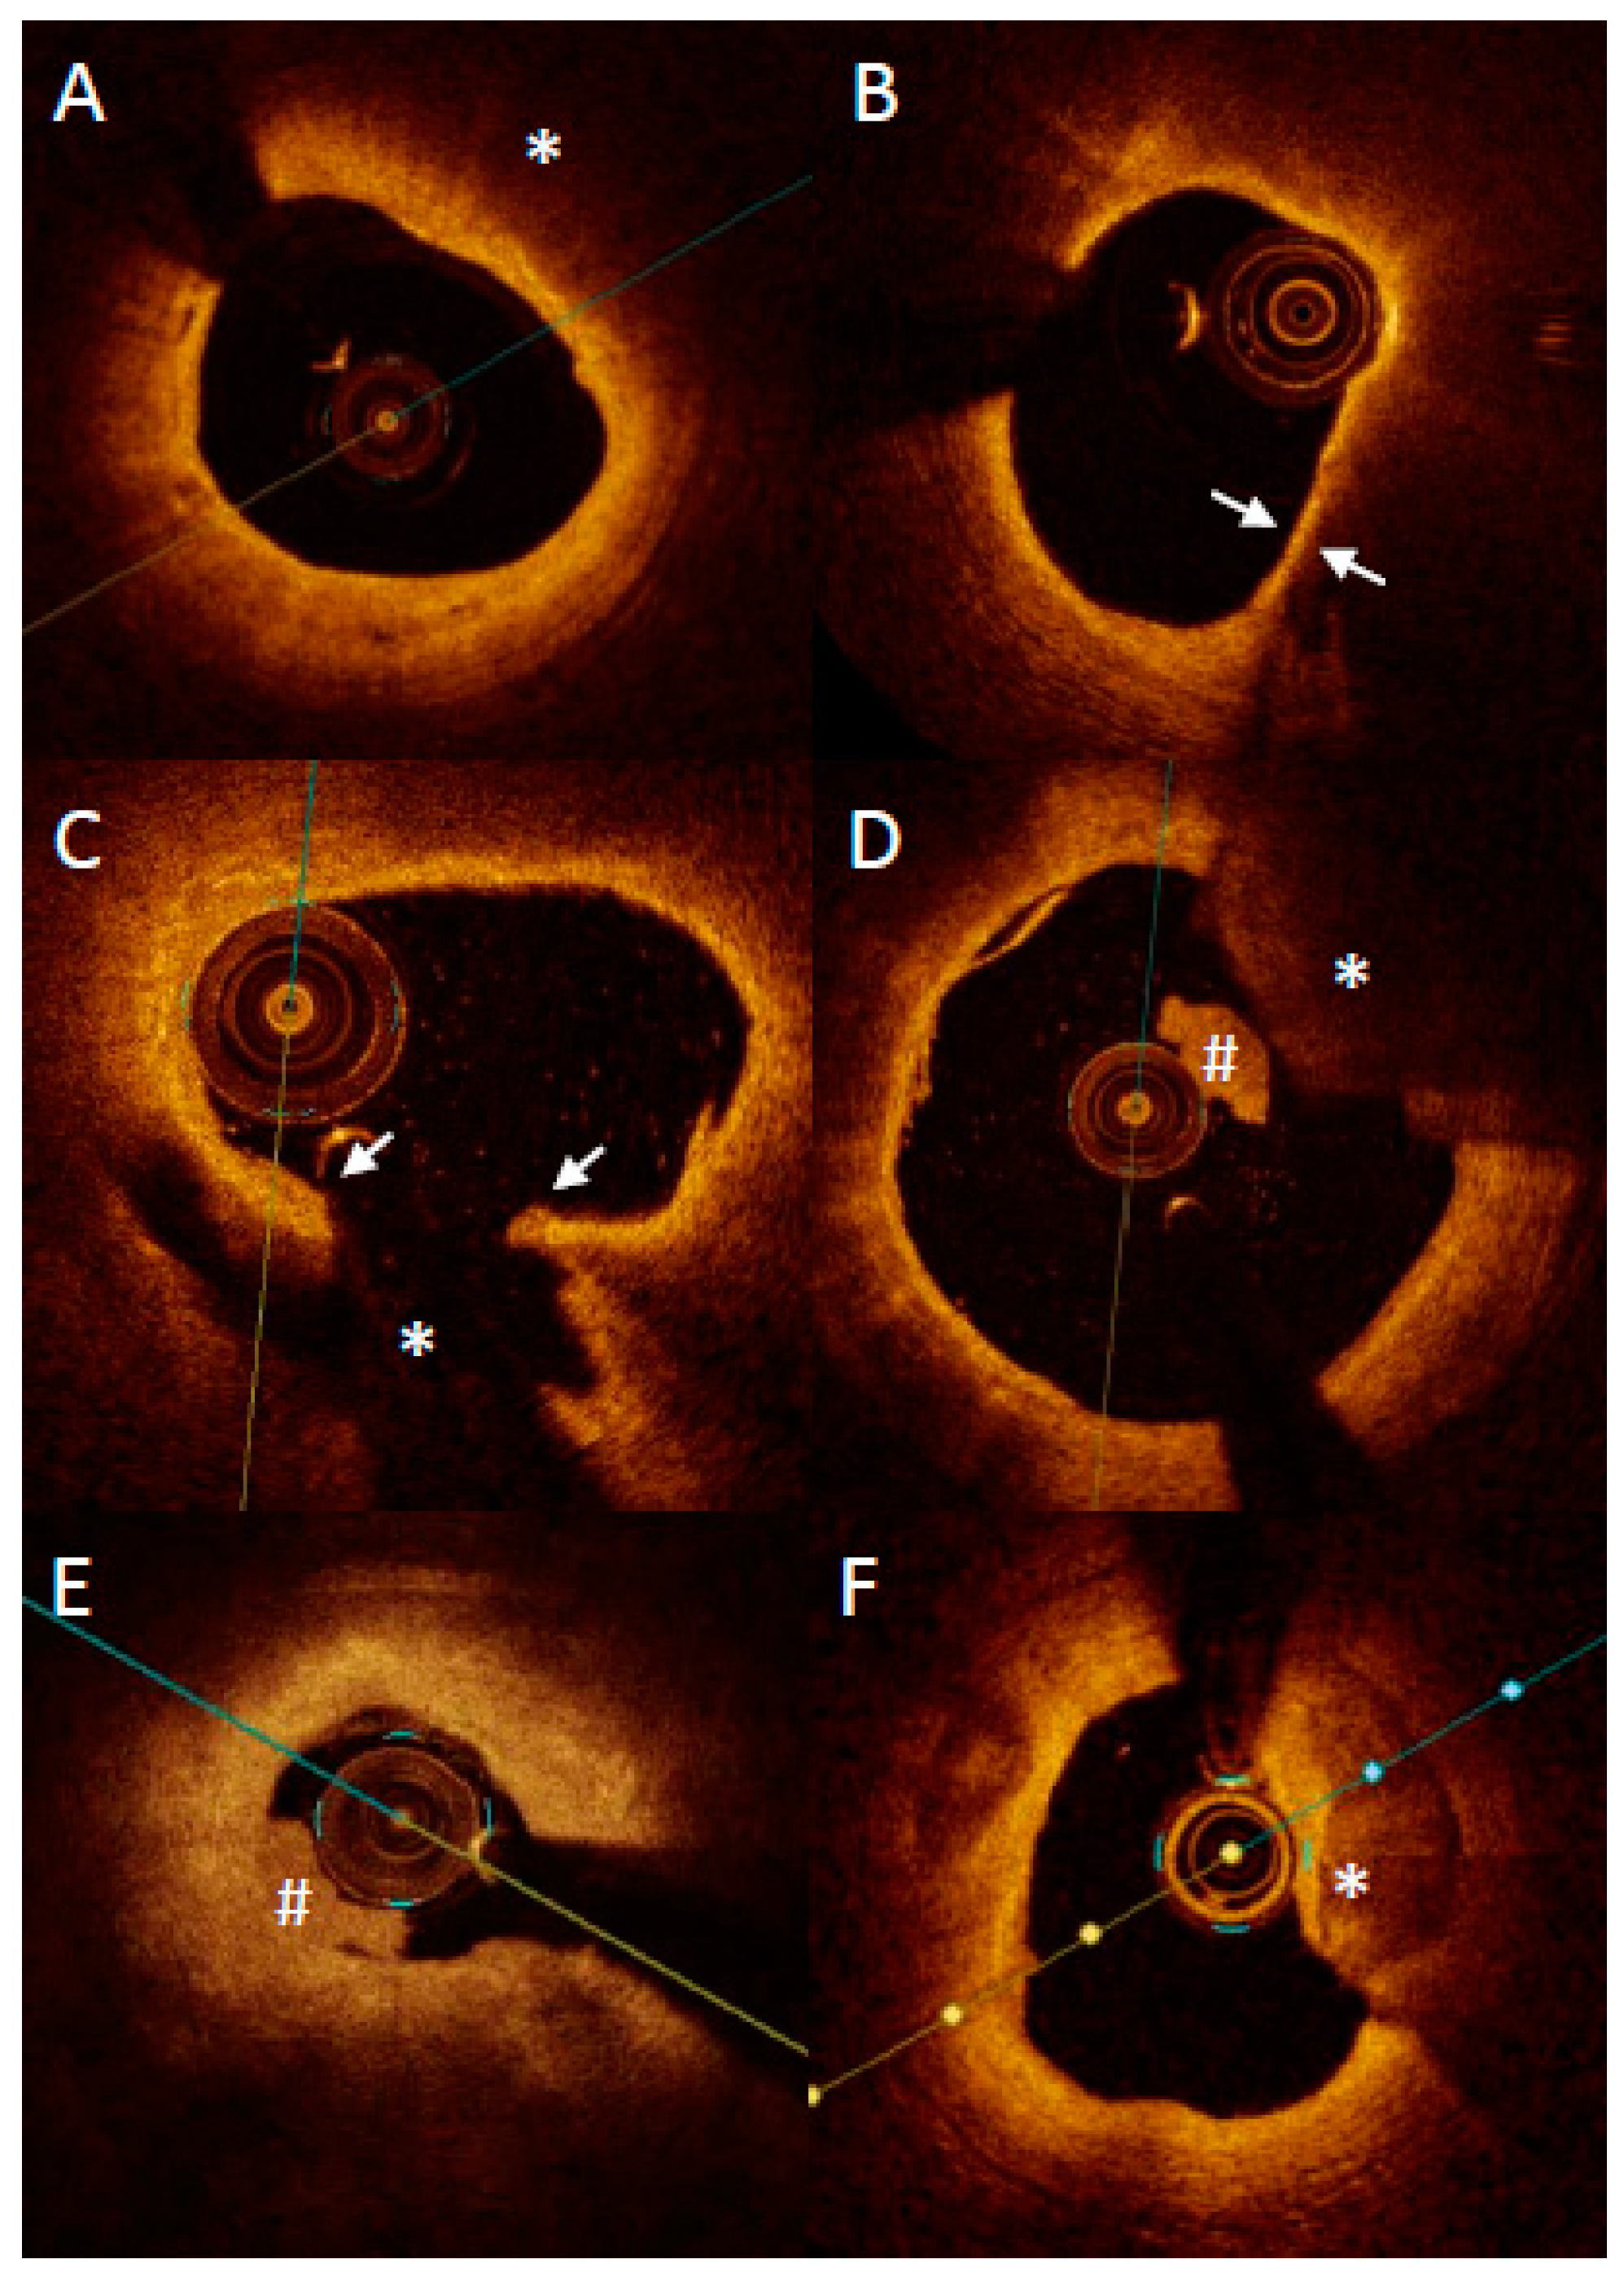

OCT with high accuracy describes the plaque composition, distinguishing between lipid-rich, fibrotic and calcified tissues (Figure 4). Lipid-rich plaques characterize a high signal attenuation in the vessel wall without clearly identified borders. A calcified lesion characterizes a high signal drop with clear borders. Fibrotic lesion characterizes a moderate signal attenuation with visible media behind the plaque [51].

Figure 4.

Representative images of optical coherence tomography findings in patients with acute myocardial infarction. Lipid plaque is characterized as signa poor regions (asterisk) with overlying signal-rich bands (A). Thin-cap fibroatheroma is defined as a lipid plaque occupying more than >90° in circumference and with fibrous cap thickness (arrows) less than a set threshold (usually 65 μm or 80 μm) (B). Plaque rupture is defined as disruption of fibrous cap (arrows) with visible cavity within the plaque ((C) asterisk). Red thrombus is described as highly backscattering structure with high attenuation ((D) asterisk), whereas white thrombus is less backscattering and has lower attenuation ((D,E) #). Erosion is described as presence of attached thrombus (usually white; #) overlying an intact and visualized plaque (E). Calcification protruding to the lumen is described as calcific nodule ((F) asterisk).

Furthermore, it enables the measurement of the thickness of the fibrous cap covering the lipid pool and thus detects thin fibrous cap atheroma (TCFA). The globally accepted definition of TCFA is the lipid-rich lesion that extends to more than 90 degrees in the vessel circumference, covered with a fibrous cap less than 65 µm thick [38]. The autopsy study presented that lipid-rich lesions with fibrous cap less than 54 µm were mostly responsible for plaque rupture and sudden cardiac deaths events [5]. For OCT, the TCFA thickness threshold is 65 µm, concerning OCT resolution, which is around 10 µm. The downside of the OCT analysis is that it relies on the observers’ experience, and sometimes TCFA might be mistaken with massive calcification within the vessel, and with artifacts, such as signal drop [52]. OCT also enables the detection of other vulnerable plaque traits such as macrophages infiltration as bright spots scattered within the lipid-rich pools, as well as neovascularization [53,54].

In addition to the TCFA identification, the OCT is enabled to identify plaque erosion, which is a cause of the myocardial infarction in about 25–40% of all cases. Plaque erosion is defined as endothelial denudation [55]. Since the endothelial thickness (5 µm) is below the OCT resolution, Nir does not visualize it directly. However, a visible thrombotic mass attached to the vessel wall, in absence of a visible fibrotic cap rupture, is suggestive of plaque erosion. Another high-risk risk trait of atheroma detectable by OCT is calcification nodule. It is a calcification spot that sticks sharply to the lumen and exposes the vessel wall for intravessel thrombosis [55]. Further, OCT with its high resolution allows for the categorization of calcification in even more detail in patients with ACS: superficial calcific sheet, eruptive calcified nodules and calcified protrusion, with the first one being most frequent and being associated with the greatest postintervention myocardial damage [10].

OCT high-resolution images reflect the history of plaque formation. OCT easily enables the identification of plaque rupture, which is presented as a disrupted cap covering the lipid pool. It also detects the silent consequence of the plaque rupture, which is the healed plaque (honey-like structure with the signal shadowing within the plaque) [56]. Importantly, healed plaques are a quite frequent finding and may be associated with panvascular vulnerability. Russo et al., in a study comprising 163 patients with stable angina, found that healed culprit plaques in coronary arteries were present in more than half of the patients (53.4%) [4]. What is more, patients with healed culprit plaques showed more multivessel disease and had more features of plaque vulnerability. Similar results were found in ACS patients where over one quarter of them had healed plaques in culprit lesions [57]. Finally, Usui et al. showed that the presence of untreated healed plaques was positively correlated with non-culprit lesion related MACE [58].